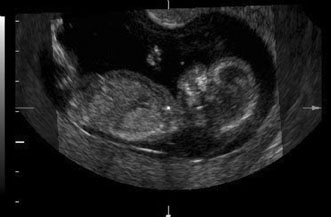

First trimester ultrasound may be performed transabdominally or transvaginally. Table 7 lists the components of a first trimester ultrasound. A crown–rump length, done between 7 and 13 weeks, can define a gestational age to within 5 days (Fig. 7).

Fig. 7. First trimester ultrasound showing crown–rump length.